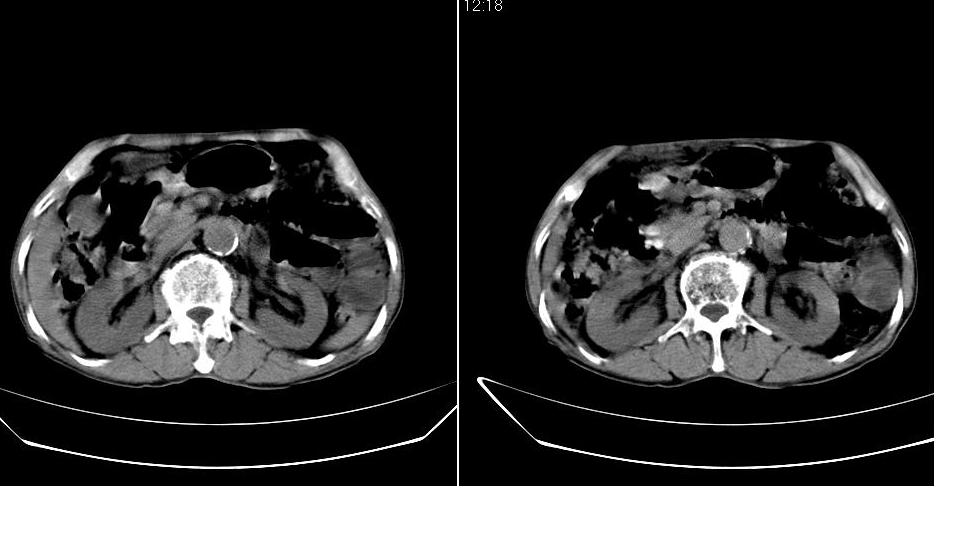

1)肝右叶前段低密度灶,不排除肝癌可能;建议查afp。2)右肾上极囊肿。

肝内胆管积气扩张,胆囊增大,肝右前叶低密度灶,逐渐强化,一元论,胆系感染,局限性肝脓肿;右肾囊肿。

考虑肝s4段肝脓肿可能?未排除肝癌。右肾上极囊肿。